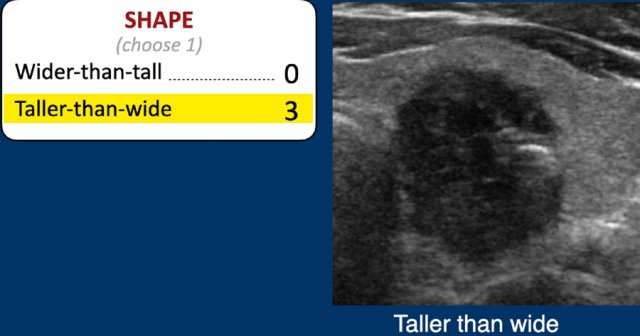

Shape

The shape should be assesed in the axial plane.

A taller-than-wide shape is a strong predictor of malignancy, and therefore gets 3 points.

Study the image and score for TI-RADS.

Scroll the image for the TI-RADS score.

3 points for the shape, which is taller than wide.